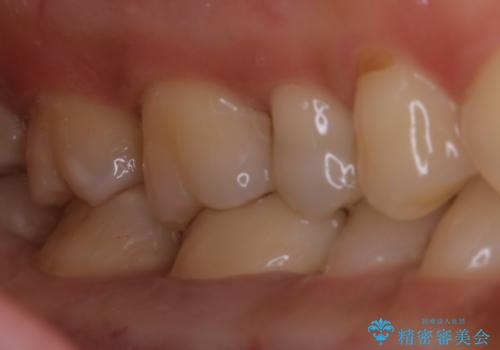

古い詰め物のやり直し治療

- 古い材料と、その下の虫歯を除去

→改めて新しい被せもの、詰め物を製作する

被せものの種類:Bellezza

詰め物の種類:e.max press-In